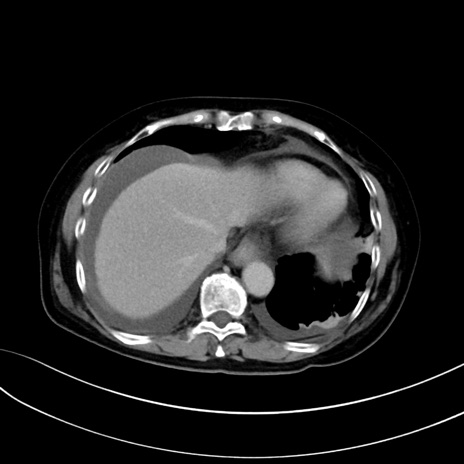

症例13 CT(横断像)1日半後